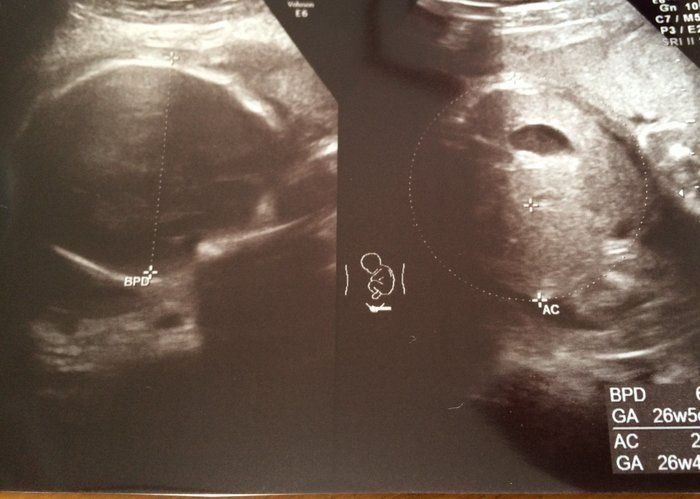

Tomomiさんの妊娠27週目のエコー写真 ついに全身が映しきれなくなる程成長してきたよ

妊娠中期に入ってから、横位(赤ちゃんが横に寝た状態)だったり逆子だったり、元気にぐりんぐりん動き回っていたベビちゃん。先生には、「そろそろ頭を下にしてくれないと、戻れなくなっちゃうかもよ~」と冗談めかして言われていたので、この時はまだあまり気にせず、指導された方向で眠る毎日でした。